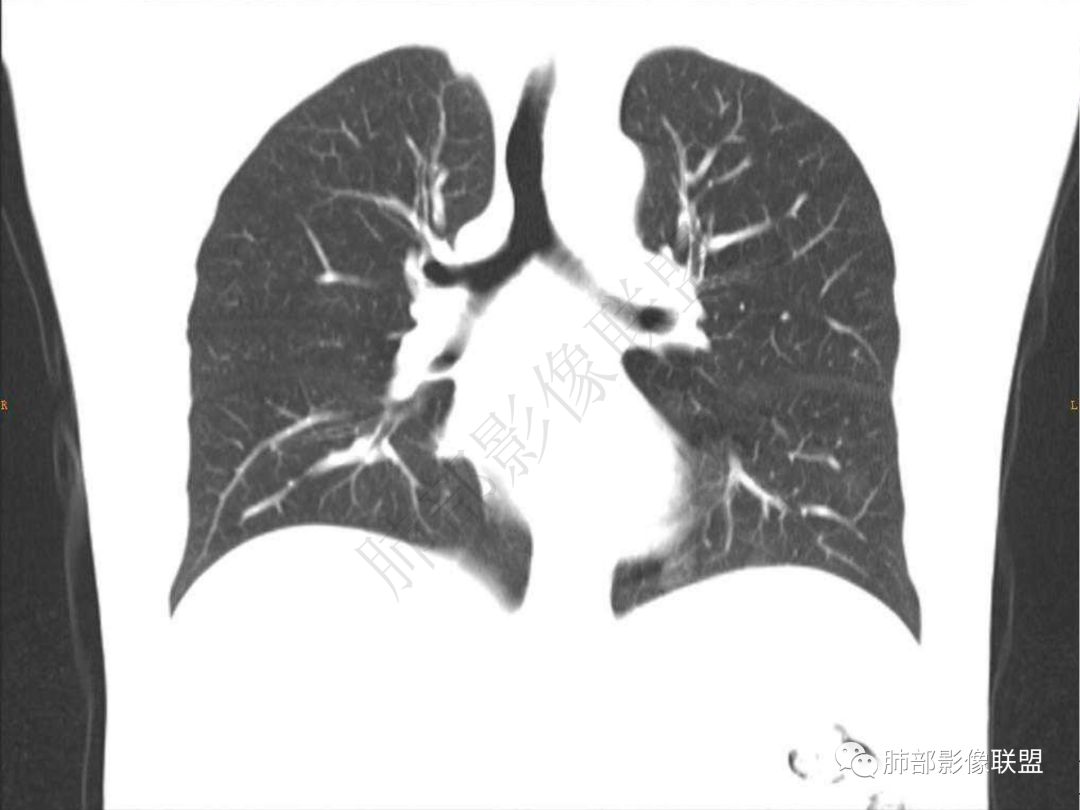

1.中年男性,咳嗽咳痰20余天,间断咯血2周

2.左肺下叶团片影,跨背段及内前基底段,实性部分类椭圆形,密度不甚均匀,可见毛刺及棘状突起,未见典型分叶及胸膜凹陷。病灶上下缘可见相应肺段支气管旁进侧出,管壁轻度增厚,未见狭窄阻塞。

3.周边较大范围磨玻璃影,边界相当模糊,小叶增厚明显。注意叶裂另一侧、左肺舌段亦可见磨玻璃影及增厚的小叶间隔。未见明确卫星病灶。

4.实性部分不均匀环形强化并显示一小范围低密度坏死区或空洞。较之肺窗,整体纵隔窗范围较小,提示病灶并不十分密实。抑或为不同时段图像。

5.双肺门及纵隔未见增大淋巴结。未见胸腔积液。